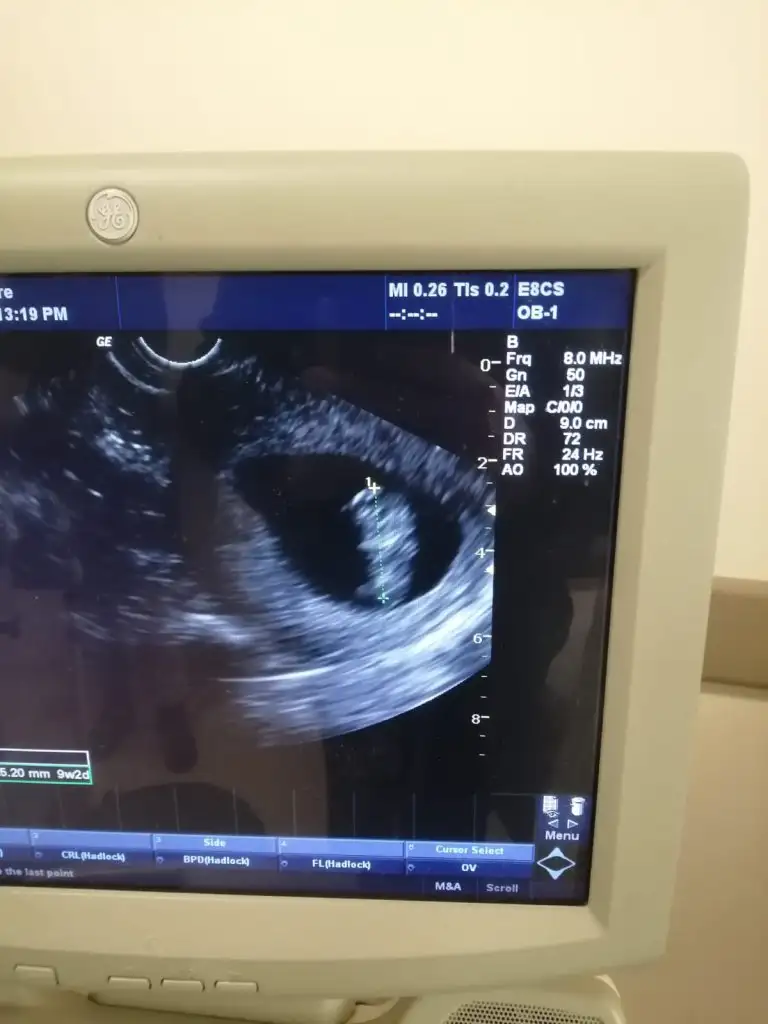

6-7 haftalık ultrason varmı yollar mısın Bi daha bakim merak ettimNisan sonu- Mayıs başıartık 18 oluyor öğreniriz heralde

ben de araya kaynasam? daha önce buraya atmıştım ama hiç tahminde bulunan olmadı.ilki 6 hafta ikincisi 7+3.6-7 haftalık ultrason varmı yollar mısın Bi daha bakim merak ettim

doktor bir şey demedi ama.Vajinal ultrason ise erkek karın ultrasonu ise kızben de araya kaynasam? daha önce buraya atmıştım ama hiç tahminde bulunan olmadı.ilki 6 hafta ikincisi 7+3.

cuma günü ikili tarama için gittiğimde görüğüm şey kordon değilse erkek gibiydidoktor bir şey demedi ama.

Kıza benziyor

Hatırlamıyorum tekrar görmem lazımCanım sen kız demiştin de ben söylememişim. Bu vajinaldi. O zaman erkek mi oluyor![]()

Bana da yorum yapar mısınKıza benziyor